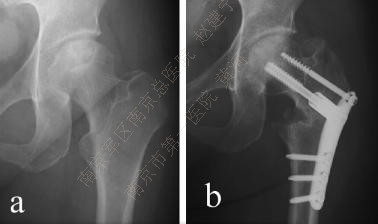

(2) 截骨

ONFH的截骨原则是纠正股骨头半脱位,恢复同心圆结构,减少负重时对坏死区的刺激。

目前临床上常用的截骨有经转子间旋转截骨(transtrochanteric osteotomy ,TRO) 及经转子间弧形内翻截骨curved varus osteotomy (CVO)两种。

TRO根据股骨轴线将股骨头颈向前方或后方旋转,使坏死区的软骨移出负重区,代之以健康的软骨。旋前或旋后取决于侧位片对坏死区的显示,如坏死位于负重区前方,则采用前方旋转截骨,反之同理。Ikemura报道优良率达80%以上。

CVO目的与TRO类似,试图将外侧相对健康的骨与软骨转移至负重区,与TRO相比,CVO能调整的范围较小,但优点是降低了对股骨头血供破坏的风险,对技术的要求也不高。